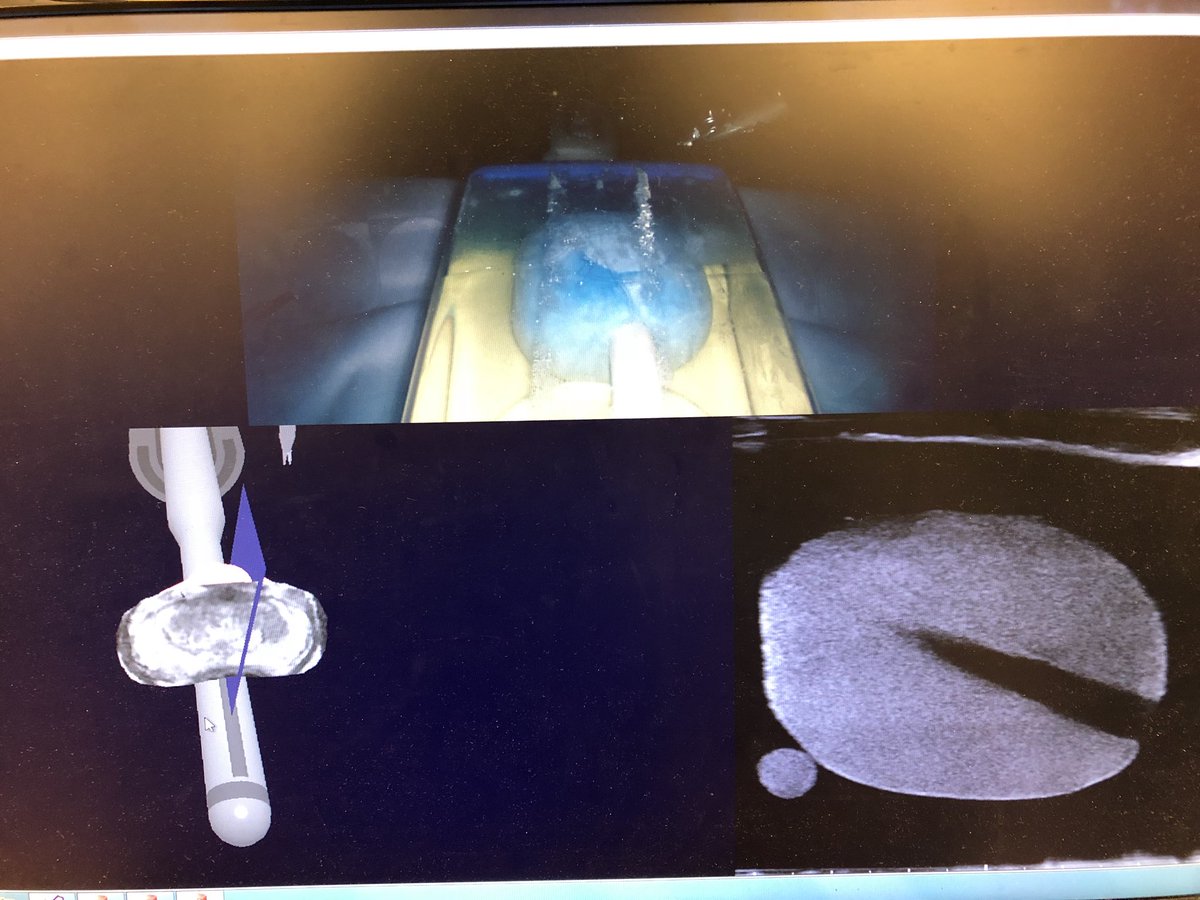

postdoc fellow@UBC, @ubcDerm research interest: skin imaging, early diagnosis of skin cancers